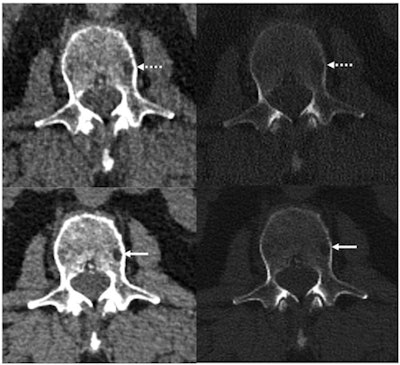

Both the conventional and the photon-counting CT images were reconstructed to 2-mm section thickness. The photon-counting images were also reconstructed at 0.6-mm thickness and then reconstructed with a convolutional neural network algorithm that reduced noise.

The investigators found that photon-counting CT had 23% lower image noise compared with conventional CT imaging at the same radiation dose. Assessment of the 2-mm images showed that photon-counting CT enabled visualization of particular bone disease features such as lytic lesions, intramedullary lesions, fatty metamorphosis, and pathologic fractures better than did conventional CT (p = 0.05); the 0.6-mm photon-counting CT images with neural network denoising produced these same results and enabled visualization of more lytic lesions compared with conventional CT in 21 of 27 patients.